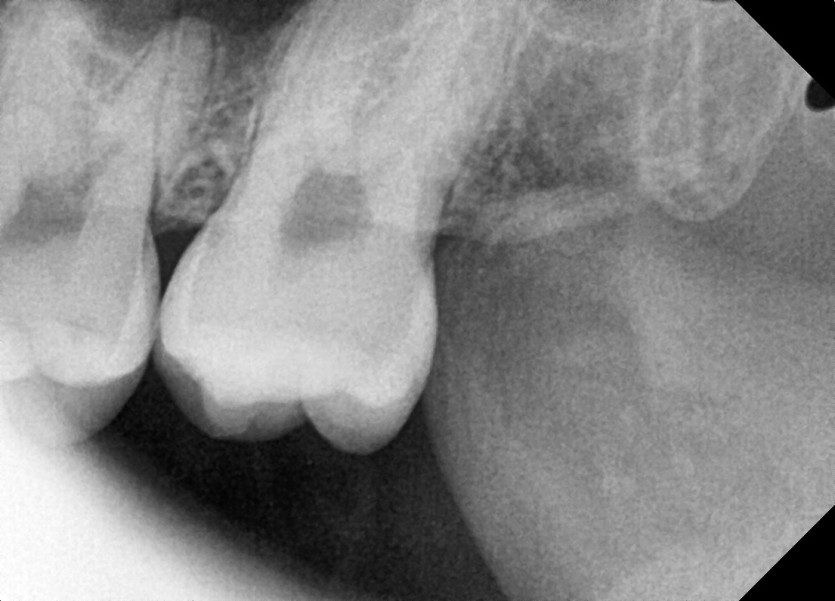

#28,38 사랑니 발치

구강 외과 전문의가 당일 발치했습니다.